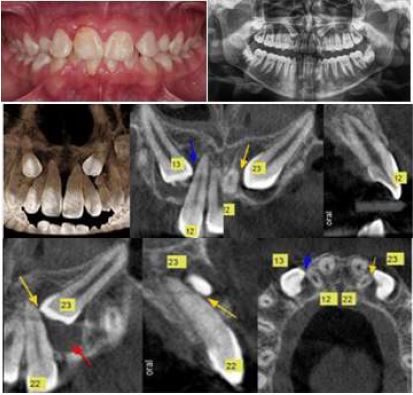

A 14-year-old boy patient attended the Orthodontics postgraduate clinic of the University of Antioquia with various dental malpositions. Medical history included allergic rhinitis. Extraoral examination showed a leptoprosopic facial pattern, straight profile, and papillary smile. Intraoral examination identified a Class I right molar relationship and a Class III left molar relationship at 2 mm, canine relationships not determinable by persistence of teeth 53 and 63, overjet 2 mm, and overbite 60%. Both the upper and lower midlines were aligned to the center. Likewise, there was moderate upper and lower crowding. When palpating the mucosa, tooth 13 was located towards the buccal but tooth 23 was not (Figure 7).

In the cephalometric analysis, the patient presented a skeletal Class II and hyperdivergent bone bases. The upper incisors were in proper position and the lower incisors were retroclined. Based on the Ericson and Kurol classification, in the panoramic radiograph, teeth 13 and 23 were located in sector I, which indicates that the prognosis for the eruption of both canines was favorable. In contrast, according to the analysis of Power and Short (11), the longitudinal axis angle of the 13 with the midline was 42° and that of the 23 was 55°, indicating that the prognosis was poor and had a high probability of retention (Figure 7).

Initial Records: Photography, Orthopantomography and Cone Beam Tomography, Case 2

FIGURE 7

The initial cone beam tomography shows 3D reconstruction, cuts in the different planes of teeth 13 and 23, and their relationship with teeth 22 and 12. The proximity of the crowns of teeth 13 and 23 with the root structures of the upper incisors are evident.

Source: the authors with permission from the patient.

In the cone beam tomography analysis (Figure 7), teeth 13 and 23 showed complete and intraosseous root formation, mesoversion, and the crown located in relation to the vestibular table. The mesial coronal contour of 13 was in close contact with the distal root profile of 12 with no signs of alteration. The mesial palatal coronal contour of 23 was in intimate contact with the distal root profile of 22, which caused a slight root remodeling, the wide pericoronal spaces suggested cystic processes.